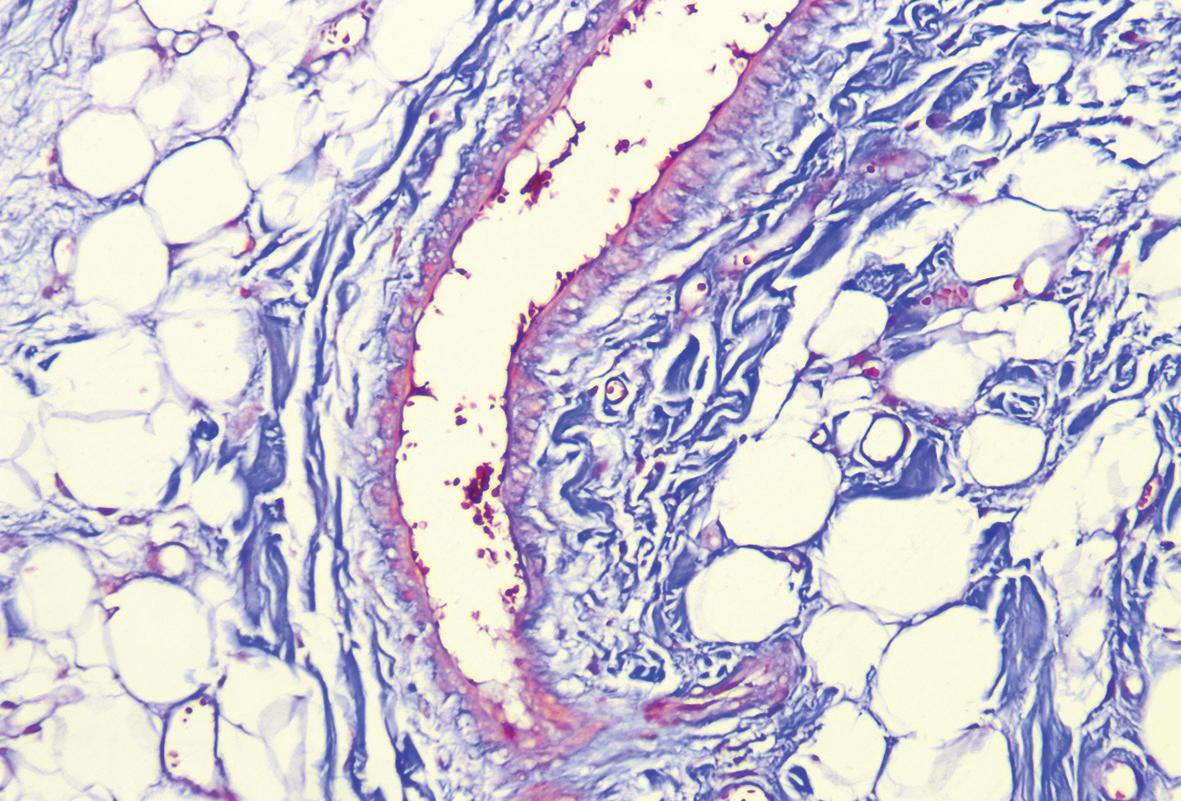

Rare angiofibrolipoma of the oral cavity: a case report

Monika Nandan

Devender Singh Chauhan